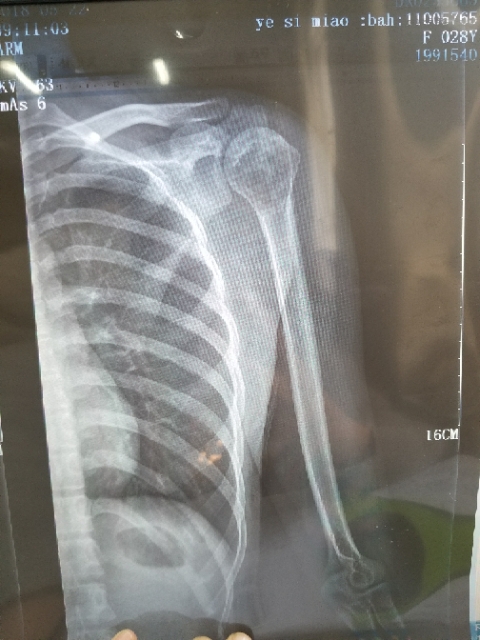

我孩子今年15岁,年初查出骨肉瘤,左腿关节处,化疗5次做载肢,手术后伤口感染误了化疗,两个多月快三个月发生肺转,如今刚住...

本人十九岁,九月十号因恶性骨肉瘤在云南省肿瘤医院做了截肢手术,后发现肺上有三个结节,一个大约一厘米,两个不足一厘米,请问...